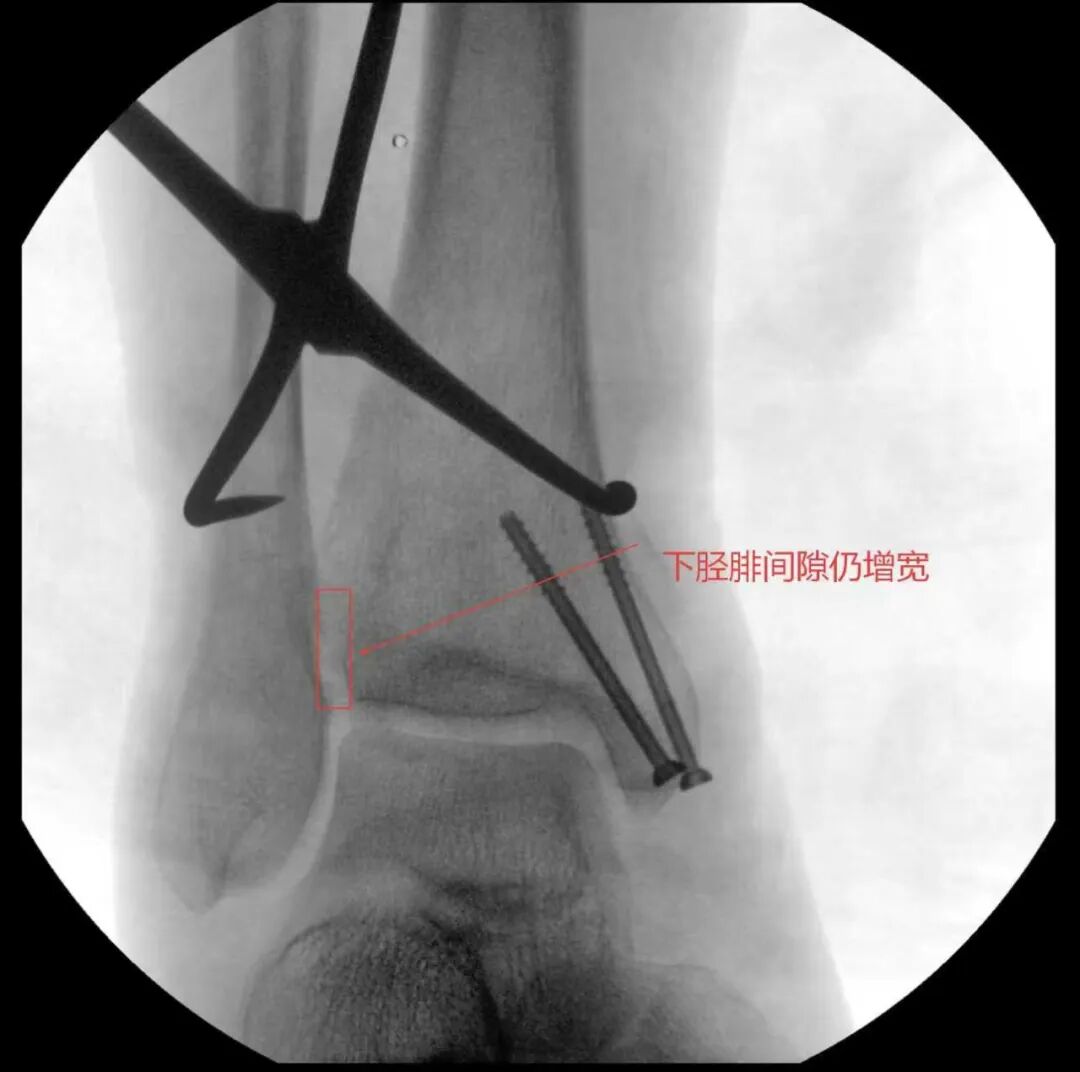

随后,医疗团队为王大爷开展手术治疗。

术中进行下胫腓拉力试验结果呈明显阳性,且复位效果未达预期,团队当机立断决定切开探查,发现前结节骨折块嵌顿于下胫腓间隙,正是阻碍复位的关键,取出骨折块后顺利完成复位,手术按规范流程顺利结束。